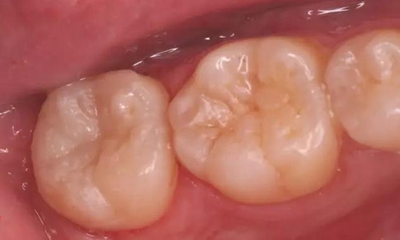

圖1 術前口內(nèi)照,37合面窩溝形態(tài)完好,

遠中牙體輕度“墨浸樣”變色,探及遠中齦下深齲洞

圖10 移除“印章”,合面窩溝形態(tài)得到較好復制

光固化,完成充填,調合、拋光